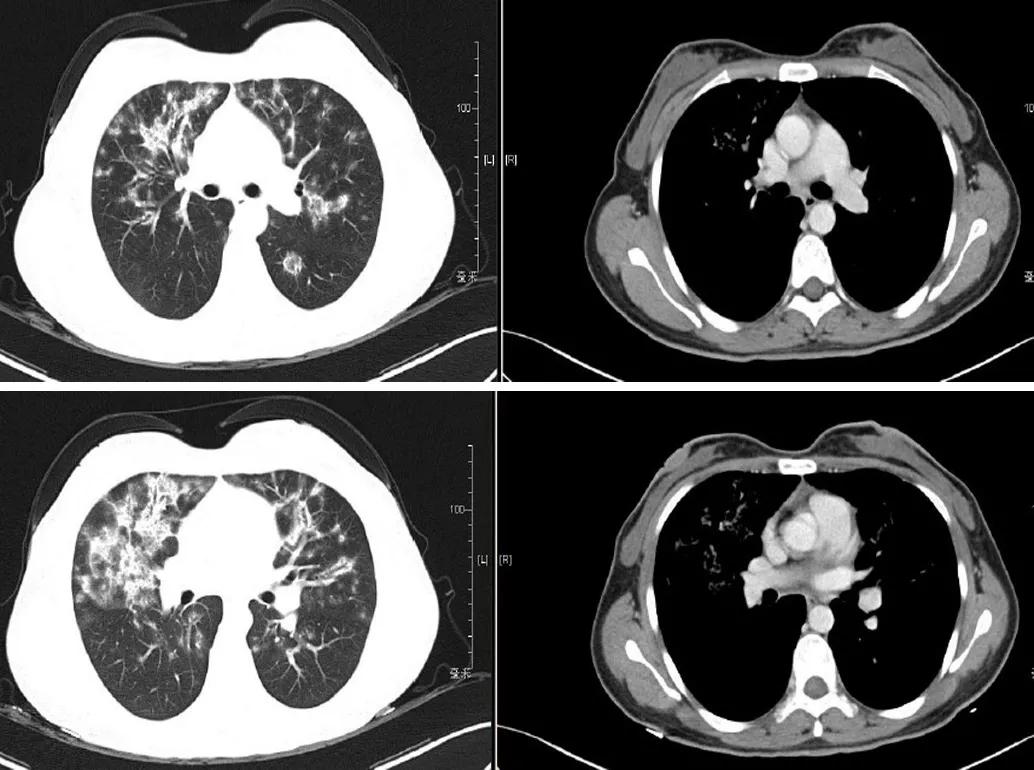

入院时胸部CT:

患者青年女性,急性起病,临床症状主要为咳嗽、气促,胸骨后疼痛,无发热、咯血、低热,血常规、炎性指标正常,胸部影像学见双肺弥漫性病变,经抗生素抗感染后病情无改善。需要考虑社区获得性肺炎(CAP)、病毒性肺炎和机化性肺炎(OP)等疾病。该患者符合社区发病,有新出现的咳嗽气促,胸部CT有新出现的斑片浸润影,符合社区获得性肺炎的初步诊断。但经验性抗感染治疗后影像学有加重,需进一步排除肺结核、肿瘤、间质性病变等的可能。社区获得性肺炎常见病原体包括细菌、非典型病原体、军团菌,初始治疗已经覆盖,但影像学仍有进展,结合病毒性肺炎影像学也可表现为两肺多发的磨玻璃实变影,故需进一步排查有无病毒性肺炎。机化性肺炎分为SOP和COP。SOP多继发于肿瘤、感染或结缔组织病相关性疾病等。该患者目前无明确肿瘤疾病,无发热脱发、皮疹、关节疼痛等症状,自身抗体阴性,炎性指标正常,故SOP的可能性不大。COP患者一般有发热、气促、干咳等,经抗感染治疗无好转,影像学可表现为下叶、外周、胸膜下多发的磨玻璃实变影,可有反晕征,游走性,该患者需考虑COP的可能。

侯医生读片还是很全面的,但读片更应该结合病史。该患者青年女性,急性起病,胸部影像提示双肺弥漫性病变,读片时应关注累及的部位,是实质还是间质、血管等。此片目前未见胸水,胸膜未累及;再看分布,两肺弥漫性分布,沿着支气管血管束,肺血管疾病基本可排除。病灶性质,磨玻璃改变,支气管壁增厚,形成牵拉性支扩,有间质累及。同时有实变,存在反晕征,结节样改变,根据影像缩小诊断范围。结合该患者影像特点,首先考虑吸入性问题,是否有慢性过敏性肺炎可能,但病史上无反复发热,反复疾病发作的情况,暂不考虑。另外还需要考虑肺曲霉病,但患者无相关暴露史,无免疫抑制基础,暂不考虑肺曲霉病。结节病和机化性肺炎也存在类似的影像学改变。其他的如急性间质性肺炎和淋巴瘤,也需要进一步鉴别。沿支气管血管束分布的还有卡伯氏肉瘤,可根据免疫细胞、HIV等后续的辅助检查进行鉴别诊断。

很高兴参加PCCM中山专场。王医生和杜医生分析很全面。作为呼吸科医生,要有疾病的诊断思路。该患者影像学表现为肺部阴影,可从肺部阴影待查的思路分析该病例。该患者青年女性,症状不典型,有胸痛,偶有咳嗽,现有实验室检测大部分为阴性,最主要特征为两肺散在肺部阴影,应从肺部阴影角度开始分析。根据杜医生做的诊断流程图,可从感染性和非感染性疾病分析。感染性疾病首先考虑细菌性感染,但经过抗感染治疗后病灶未见吸收,细菌感染可能性不大。其他的如隐球菌、结核、真菌感染等,结合患者症状和血化验等指标,考虑感染的可能性比较小。非感染性肺部阴影,首先考虑肿瘤,肿瘤临床表现多样,存在炎症样肿瘤可能。另外是否存在吸入、药物因素,鉴别诊断应该考虑的因素。肺部阴影中还有一些是与间质相关,如特发性间质性肺炎、隐源性机化性肺炎等,这些疾病有待进一步病理诊断。